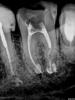

Dmitry 72 Опубликовано 15 декабря, 2012 Автор Поделиться Опубликовано 15 декабря, 2012 Дали снимок, но я, чесно говоря, не уверен, что это тот снимок. Про кисту речь не шла. К какому хорошему мастеру можно поехать на диагностику и снимок там же сделать? Ссылка на комментарий

DmitrySH Опубликовано 15 декабря, 2012 Поделиться Опубликовано 15 декабря, 2012 (изменено) Дали снимок, но я, чесно говоря, не уверен, что это тот снимок. Про кисту речь не шла. К какому хорошему мастеру можно поехать на диагностику и снимок там же сделать?Если на снимке тот зуб котором разговор, то..Зуб вполне " спасабельный" ну не на 100% конечно, но шансы есть. Кисты тут не вижу. "белое" за прелелами зуба скорее всего Метапекс. Изменено 15 декабря, 2012 пользователем dmitrySH Ссылка на комментарий